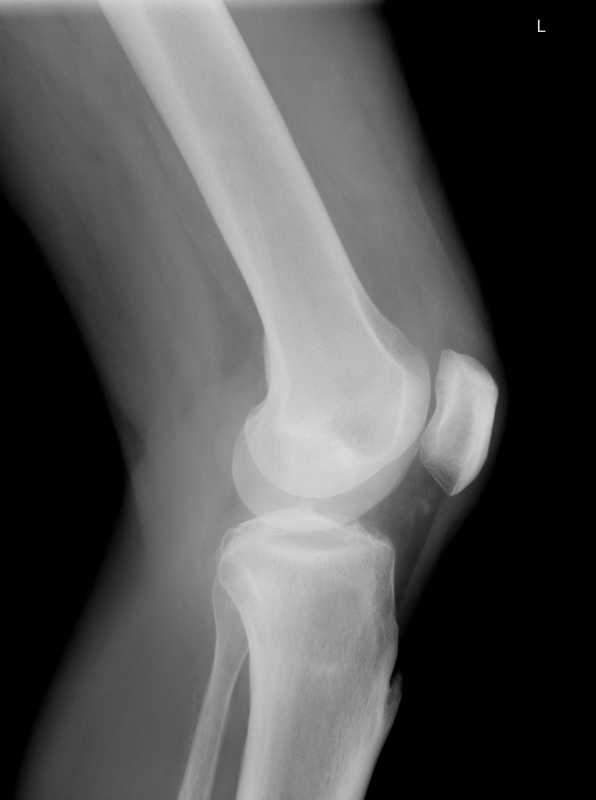

Anatomicky je Achillova šlacha spojením šlach svalů Gastrocnemius a Soleus.

Přibližně 5 cm nad ukončením běžecké obuvi v místě paty se šlachy spojují v jednu - Achillovu šlachu.

Tyto spojené šlachy jsou "obaleny" jednou vrstvou buněk, která se nazývá Paratenon. Toto "opláštění" je bohaté na cévy potřebné k vyživování šlachy.

Samotná šlacha je tvořena ze dvou typů pojivové tkáně známé jako kolagen typu 1 a kolagen typu 3. Zdravá Achillova šlacha je z 95% tvořena kolagenem typu 1, který je silnější a pružnější než typ 3.

Křížová vazba a paralelní uspořádání kolagenových vláken typu 1 dodává Achillově šlaše její sílu.

Na rozdíl od drtivé většiny šlach v těle je Achillova šlacha jedinečná tím, že v místě, kde se svaly Gastrocnemius a Soleus spojují, se šlacha otáčí o 90 stupňů ještě předtím, než se připojí k zadní části paty. Toto extrémní zkroucení výrazně zvyšuje její účinnost při běhu, protože tak umožňuje, aby šlacha fungovala jako pružina ve fázi odrazu a dopadu.

V závislosti na místě poškození jsou poranění Achillovy šlachy rozdělena do několika kategorií:

- inzertní tendinitida

- paratenonitida

- neindukční tendinóza

Jak naznačuje název, inzertní tendinitida se týká zánětu na místě upevnění Achillovy šlachy na patě. Naštěstí tento typ poškození Achillovy šlachy je relativně neobvyklý.

Nejčastějším typem poškození Achillovy šlachy je paratenonitida. Toto zranění představuje zánětlivou reakci ve vnějším plášti buněk obklopujících šlachu. Zánět má za následek viditelnou hrudku. Tato hmota představuje lokalizované zhuštění paratenonu v reakci na mikrotrauma. Pokud v běhu budeme nadále pokračovat, tak velikost hrudky se bude zvětšovat, a nakonec bude bolest tak silná, že nám znemožní běhat (to ještě nemluvíme o tom, že díky "uhýbání" této bolesti při běhu, si můžeme přivodit další zdravotní komplikace).